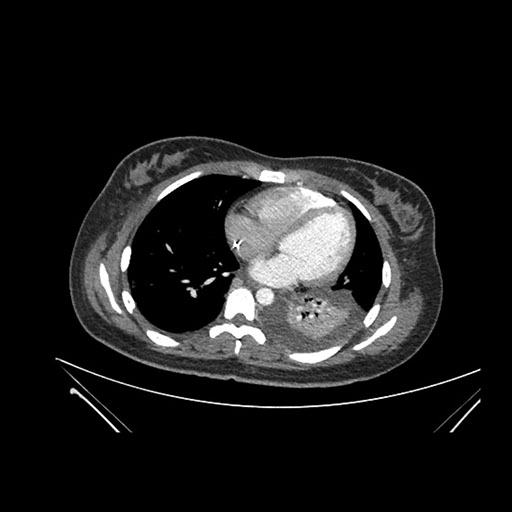

Imaging Analysis

Look through the patient's CT scan to identify any areas of concern for the necessary procedure.

Axial Venous

Based on initial findings, which issue(s) would you be most concerned about?